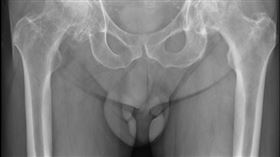

長輩最怕摔!醫:開刀後做1事避長期臥床

髖關節骨折好發於65歲以上長者,而因女性骨質疏鬆率較...

她出國前跌倒竟髖部骨折!秒懂3大NG行為

一名55歲女士因經濟寬裕選擇提前退休,準備到處旅行的...